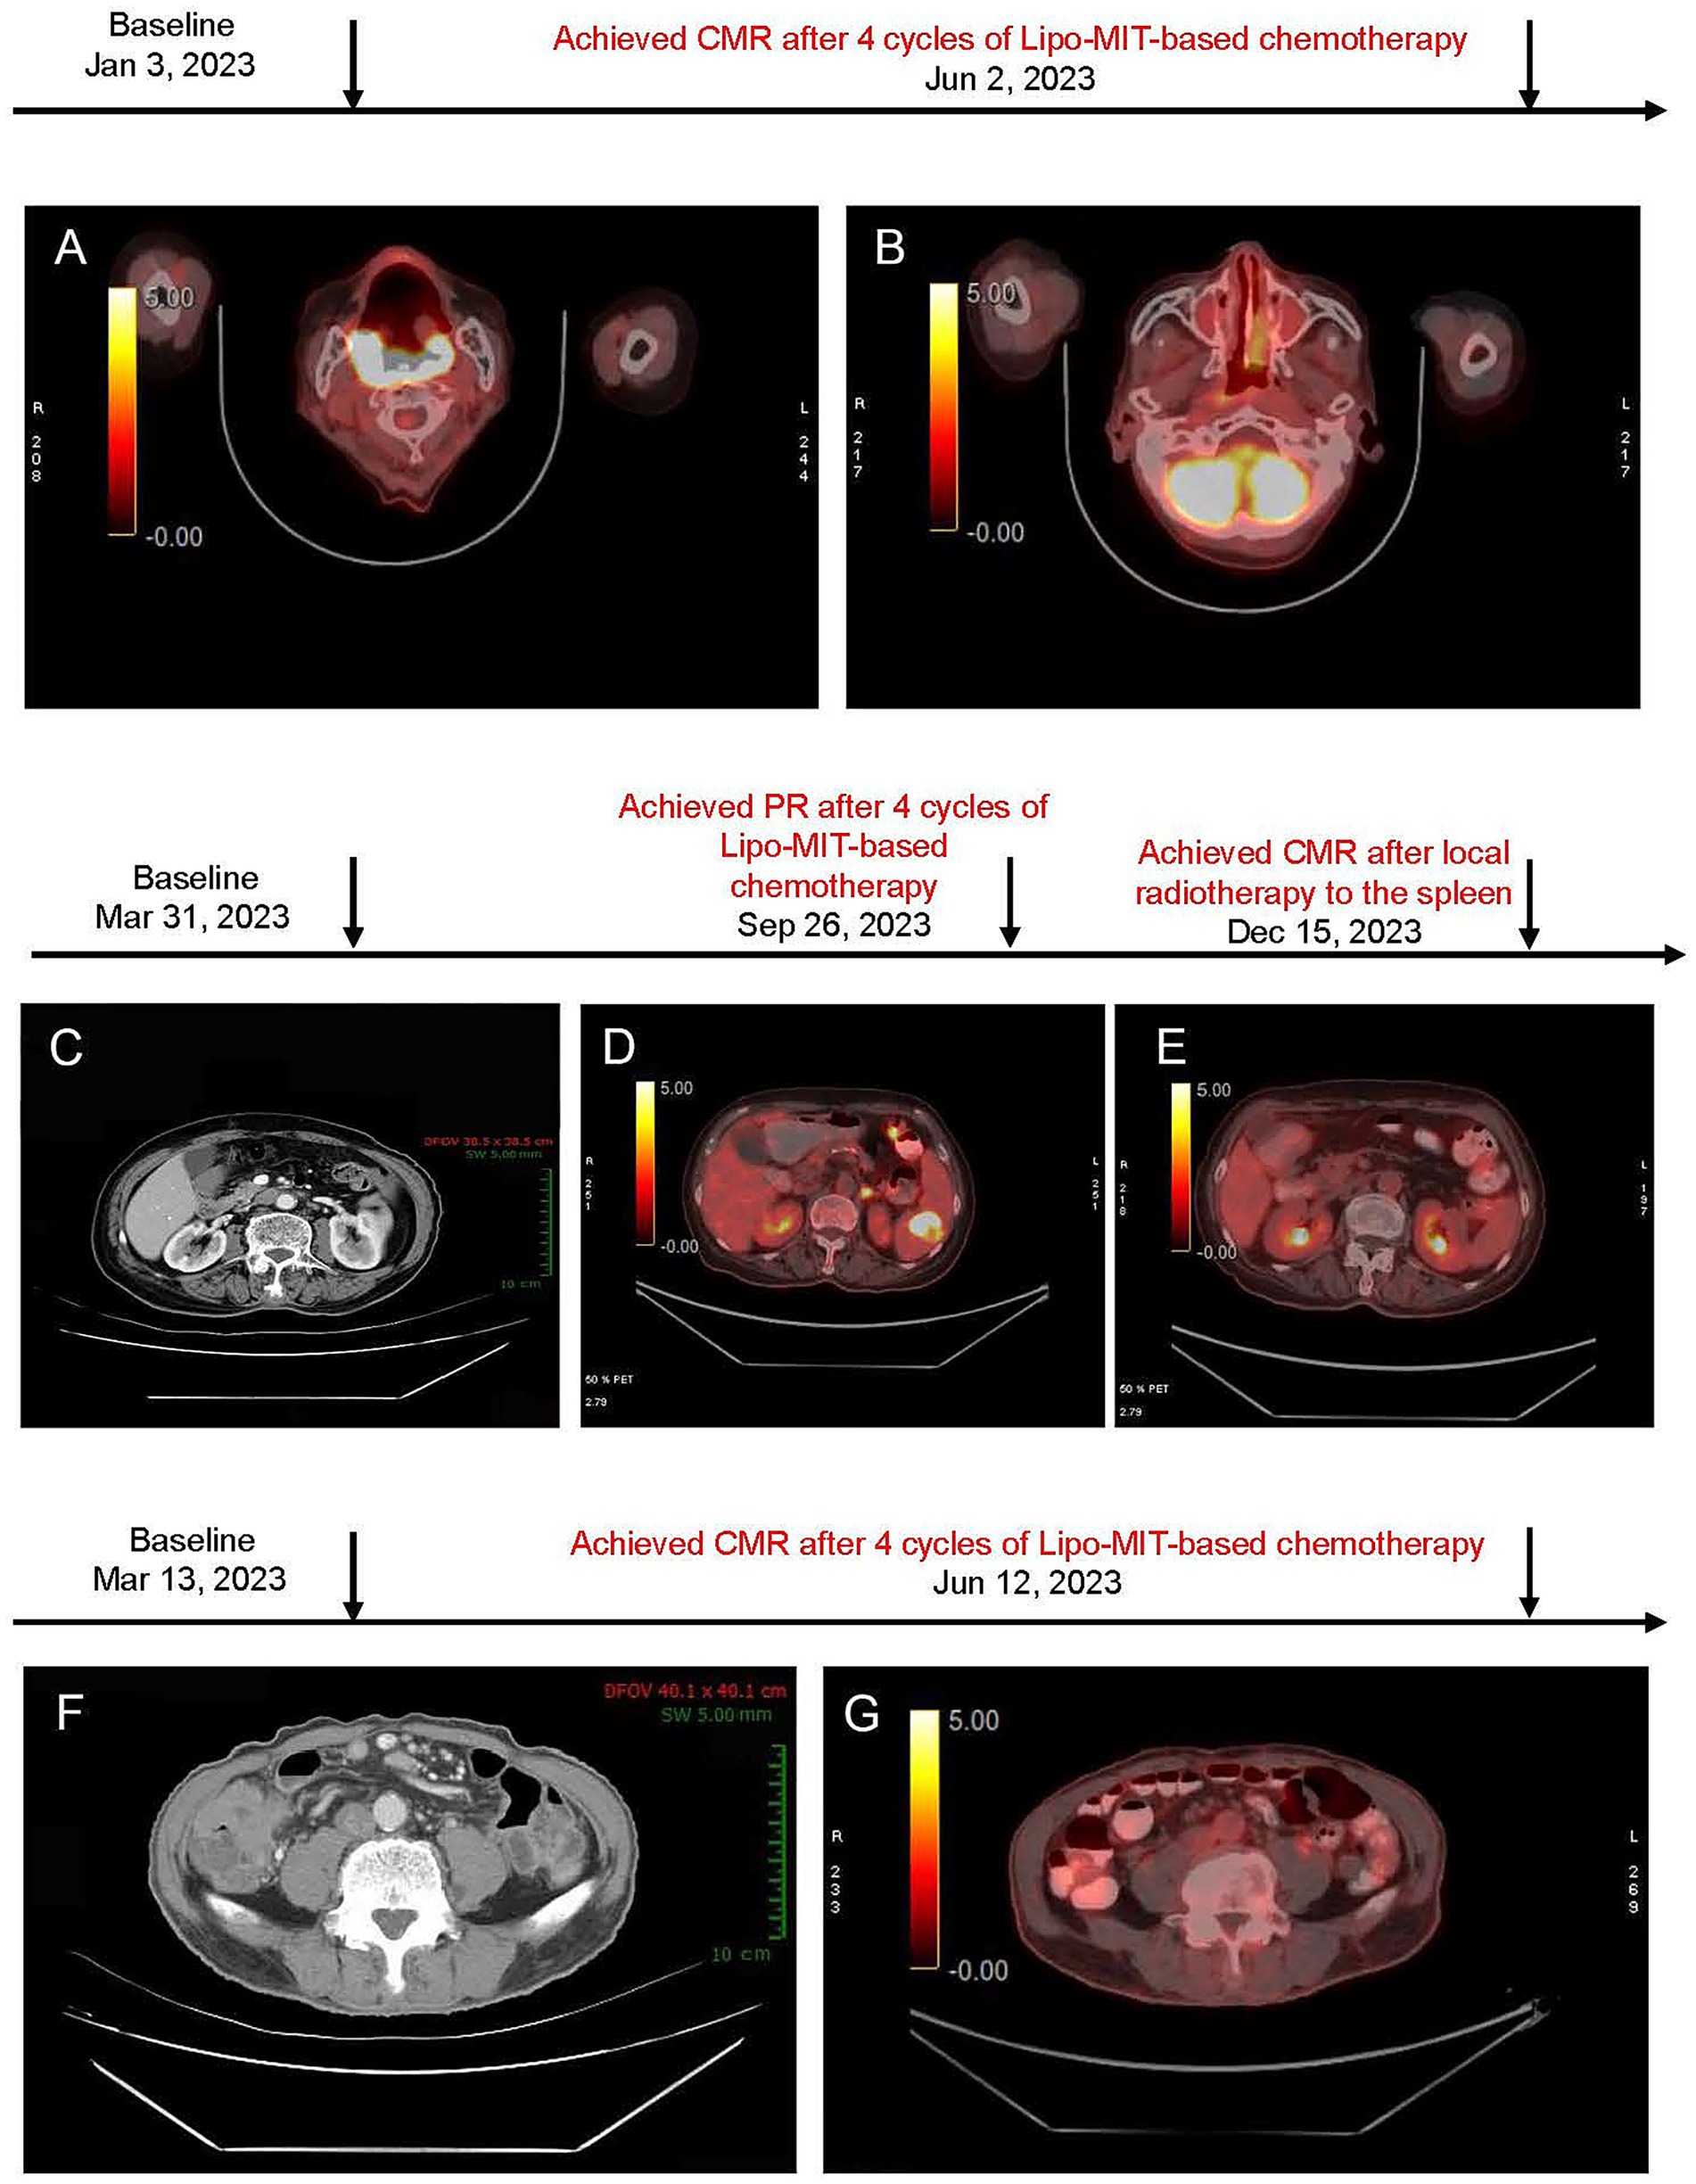

In January 2023, she presented with recurrent DLBCL involving the right nasopharynx and cervical lymph nodes, confirmed by PET/CT [maximum standardized uptake value (SUVmax) 31.5] and biopsy as stage IV disease (Figure 1A). The echocardiogram revealed a calcified posterior mitral valve, mild mitral regurgitation, left ventricular diastolic dysfunction (grade 1), and a premature beat; the left ventricular ejection fraction (LVEF) was 67% (Table 1). Baseline blood tests revealed leukopenia [white blood cell (WBC) 2.86 × 109/L] and anemia (hemoglobin 91 g/L; Supplementary Table S2).

Figure 1

(A,B) PET/CT images before and after mitoxantrone hydrochloride liposome-based chemotherapy for case 1. (A) Baseline PET/CT image (January 3, 2023) showed soft tissue thickening in the right nasopharynx, soft palate, bilateral oropharynx, base of tongue, and the right parapharyngeal space. (B) Post-treatment PET/CT image (June 2, 2023) demonstrated that the right retropharyngeal group and bilateral deep cervical chains were observed with multiple lymph nodes (no increased standardized uptake value, and maximum short-axis diameter approximately of 0.5 cm). Deauville score = 3. (C–E) Imaging findings of the neck, chest, abdomen, and pelvis in case 2. (C) Baseline CT scan (March 31, 2023) revealed a Splenic mass (~ 3.2 × 2.8 cm). (D) After six cycles of treatment (September 26, 2023), PET/CT showed low-density lesion within the spleen (~1.6 × 1.0 cm) and increased uptake (maximum SUV of 8.5) were observed, suggesting the presence of residual tumor (Deauville score = 5). This patient achieved PR. (E) Follow-up PET/CT (December 15, 2023) demonstrated further reduction in lesion size, a slightly low density in the spleen with diminished size compared to the previous assessment, and no obvious signs of increased metabolic activity (Deauville score = 1). This suggests an improvement post-treatment. (F–G) Imaging findings of neck, chest, abdomen, and pelvis for case 3. (F) Baseline CT scan (March 13, 2023) showed significant thickening of the ileocecal wall (maximum SUV 2.1 cm). Surrounding lymph nodes were observed (maximum short-axis diameter ~ 0.8 cm); (G) Post-treatment PET/CT scan (Jun 12, 2023) revealed the thickening of the ileocecal wall with diffuse uptake (maximum SUV of 3.2); multiple lymph nodes around were identified with no obvious increased uptake (maximum SUV of 2.2; maximum short-axis diameter ~ 0.5 × 0.5 cm; Deauville score = 3).

A PET/CT scan after two cycles showed a remarkable reduction in tumor size and confirmed complete metabolic remission (CMR) according to Lugano 2014 criteria at four cycles (Figure 1B). The progression-free survival (PFS) and duration of response (DoR) were both 11 months.

An 82-year-old female (Supplementary Table S1), weighing 52 kg, with a BSA of 1.52 m2, and a KPS of 80, classified as fit based on sGA, presented at Sanhuan Cancer Hospital on March 31, 2023. She was diagnosed with Stage III DLBCL according to the Lugano 2014 staging system [non-germinal center B-cell-like (non-GCB), international prognostic index (IPI score = 2)]. CT imaging revealed a splenic lesion (3.2 × 2.8 cm) and multiple lymph node involvements, including supraclavicular, axillary, mediastinal, pulmonary hilum, and retroperitoneal areas (Figure 1C).

The patient achieved partial remission after four cycles (Figure 1D), and disease progression was noted at the splenic site at cycle 6. Finally, after local radiotherapy to the spleen for a month, she achieved CMR confirmed by PET/CT (Figure 1E). The PFS and DOR were 22 months and 14 months, respectively. The patient remained in complete remission as of June 13, 2024. However, disease progression was observed by February 2025 during follow-up evaluations, and subsequent second-line treatment with the POLA-BR regimen (polatuzumab vedotin, bendamustine, and rituximab) was performed according to the guideline. The treatment is ongoing.

He presented with stage II DLBCL involving the ileocecal region and peripheral lymph nodes. The tumor exhibited double expression of MYC and BCL2. Baseline PET/CT showed markedly increased metabolic activity in the thickened ileocecal intestinal wall (SUVmax 23.2) with associated small lymphadenopathy (Figure 1F). Furthermore, his echocardiogram demonstrated mild regurgitation in both the mitral and aortic valves with left ventricular diastolic dysfunction (grade 1); the LVEF was 74% (Table 1).

The patient reached PR at cycle 2 and achieved CMR at cycle 4 (Figure 1G; June 12, 2023). As of June 13, 2024, the patient remained in complete remission, and at the most recent follow-up in March 2025, there was no evidence of disease recurrence. The PFS was over 28 months, and the DoR was 24 months.